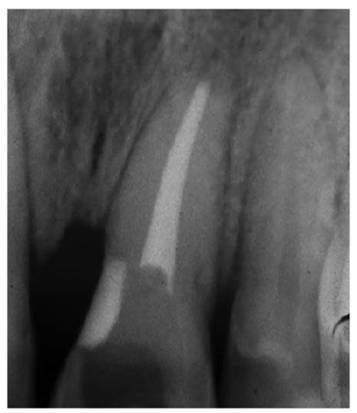

youngster's nonrestored tooth (Figures 19-46A, and 19-46B) would differ considerably from

that of the same tooth with multiple restorations in a middle-aged person (Figures 19-47A, and 19-47B

Figure 19-46A: Access cavity in a traumatized unrestored maxillary central incisor of a 16-year-old male.

Figure 19-46B: Radiograph of the same tooth showing a large pulp chamber and root canal.